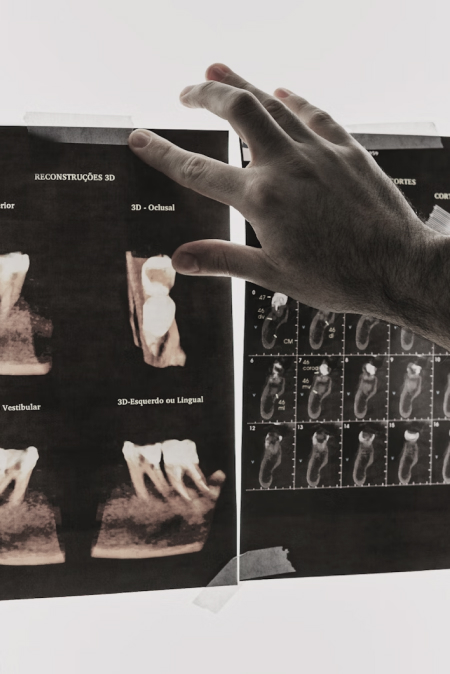

난이도 높은 사랑니 발치도, 정밀 CT 진단과 숙련된 수술 경험으로

대학병원 의뢰 없이 한 공간에서 바로 진행합니다.

구강 검진, 촉진, 교합 검사 또는 파노라마, CBCT, MRI 촬영을 통해

눈에 보이지 않는 부위까지 선명하게 관절 및 디스크 상태를 확인합니다.

정밀 진단

- 구강 검진, 촉진, 교합 검사

- 필요 시 파노라마, CBCT, MRI 촬영을 통해 관절 및 디스크 상태 확인